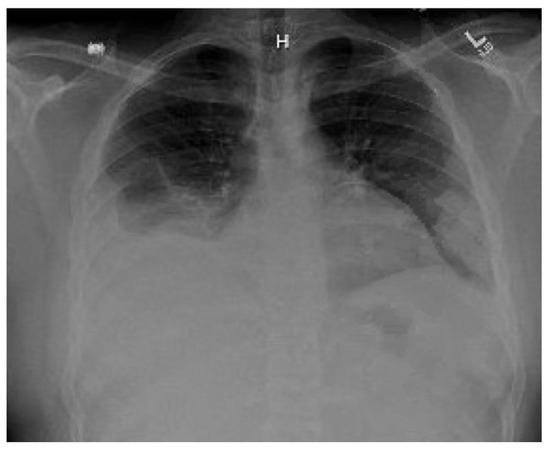

Introduction: Hypertension is occasionally associated with congenital hydronephrosis. Case report: The authors report a four-month-old boy with severe left congenital hydronephrosis and transient hypertension triggered by his first urinary tract infe...